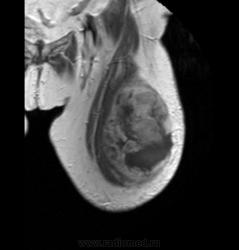

Пациентке 79 лет, с жалобами на болезненность и наростающую припухлость по передне-латеральной поверхности левого бедра в течении 3х месяцев, было проведено исследование в октябре по поводу объемного образования мягких тканей левого бедра.

Т1/ВИ

В толще проекции латеральной головки четырехглавой мышцы визуализируется объемное образование неоднородной с визуализируемой псевдокапсулой, интимно прилежит к бедренной кости, без признаков нарушения целостности кортекса, костный мозг интактен. В наружных отделах прерывание капсулы с выходом на поверхность кожных покровов. Неравномерно контрастируется. Похожа на рабдомиосаркому.

Гистология: фибро-саркома. После первого исследования пациентка была прооперирована и ей была проведена химиотерапия совместно с лучевой. Второе исследование проведено в конце ноября. Ваше мнение?

Удаляли субтотально?Есть образование с аналогичным типом контрастирования.

Не знаю какому правилу придерживаются при оперативном вмешательстве такого образования но в данном случае тянет на продолженный рост, мышечные сухожилия передней группы мышц бедра почему остались.